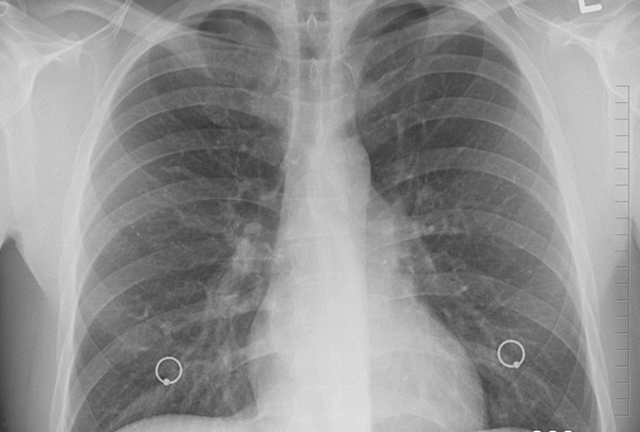

Die Lunge

Atmung, Atemwege, Lunge und Zwerchfell